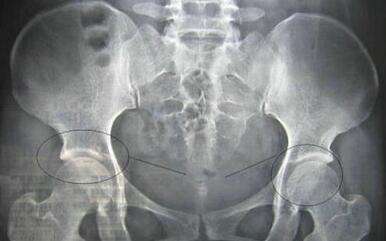

(图:入院检查显示王先生髋关节出现关节炎症)

【入院检查】

检查:白细胞偏多,血沉及C反应蛋白显著偏高,HLA—B27检查呈阳性,球蛋白升高,类风湿因子阴性。

诊断:强直性脊柱炎